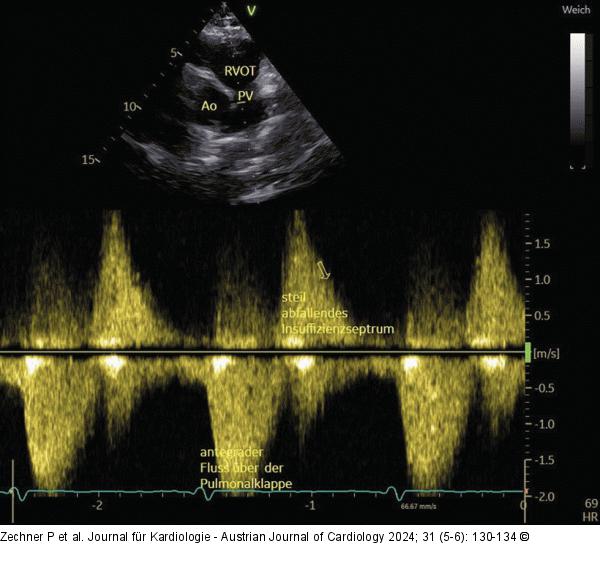

Abbildung 5: Echo Gleiche Patientin wie Abb. 4, PSAX; bei einer schweren PI zeigt sich das steil abfallende Insuffizienzspektrum, am Ende der Diastole kein Rückfluss mehr. |

Gleiche Patientin wie Abb. 4, PSAX; bei einer schweren PI zeigt sich das steil abfallende Insuffizienzspektrum, am Ende der Diastole kein Rückfluss mehr. |